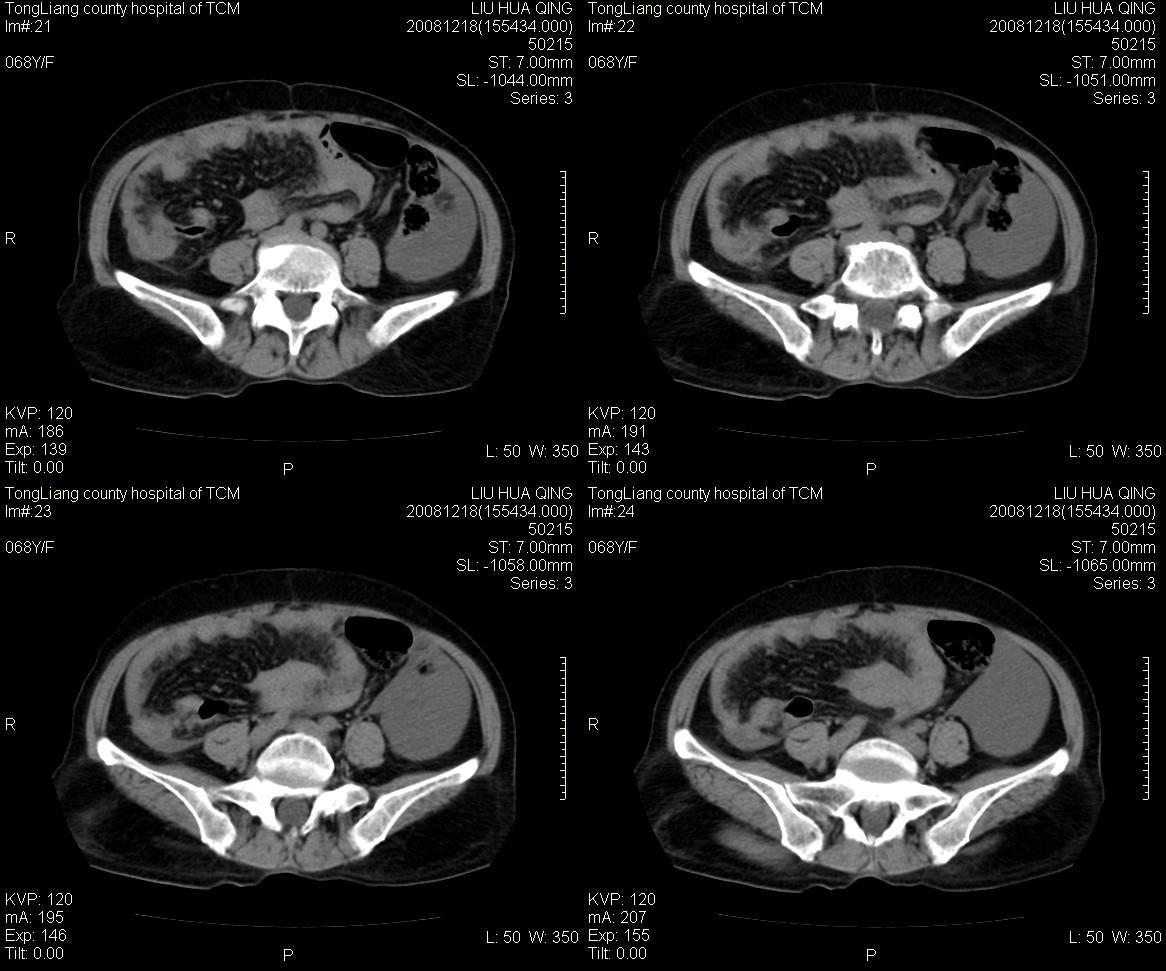

女,68y,下腹疼3月,一月半前院外ct示上腹未见异常。近1月来,症状加重。4天前入院,b超示胸腹水。今日呕吐频繁。  生化检查:  结核抗体阴性,血沉18mm/h, 癌胚抗原阴性,胸水细胞学检查见多数淋巴细胞。 白细胞总数5.4x10^12/l,血红蛋白104g/l.

患者右中腹部肠管聚集,内密度不均,可见片絮状及结节样增密影,小肠壁增厚,与之相邻处有软组织影。

腹腔积液可以肯定,原因?右侧下腹肠壁增厚,周围脂肪密度增高,粘连坏死?---梗阻坏死(不像)还是血栓坏死,占位?期待结果。

肠系膜可见梳征,不除外克罗恩氏病.腹水,建议气钡双重造影,灌肠.

1)右侧腹腔前部见类似“网膜饼”样改变,考虑网膜转移瘤。2)腹水。

腹膜污染[大网膜增厚可见污垢征及小班结与饼片影,肠系膜增厚],大量腹水。考虑癌性腹膜炎,建议查腹水。结核待排.注意上腹部及胃肠道检查